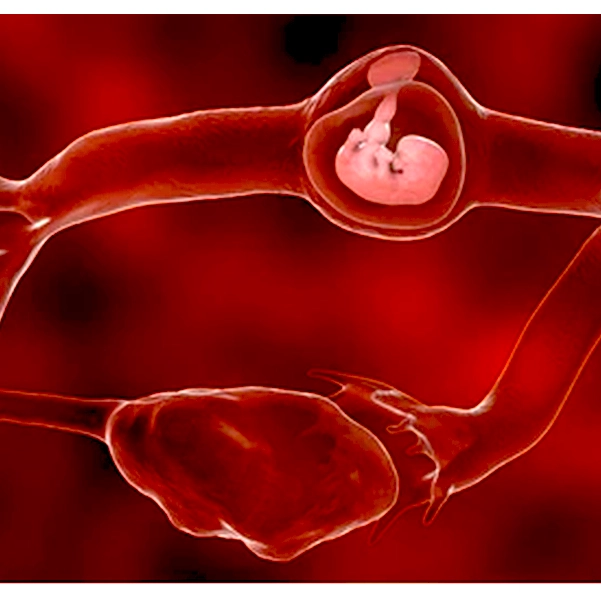

حاملگی خارج رحم (Ectopic Pregnancy) زمانی رخ میدهد که تخمک بارور شده به جای قرار گرفتن در داخل رحم، در جای دیگری مانند لولههای فالوپ، تخمدان یا حتی شکم کاشته شود. این وضعیت میتواند بسیار خطرناک باشد و نیازمند توجه فوری پزشکی است. علاوه بر اهمیت رعایت نکات مربوط به تغذیه در دوران بارداری برای سلامت جنین، در این شرایط توجه ویژه به علائم حاملگی خارج رحم ضروری است. در ادامه به مهمترین علائم این بیماری اشاره میکنیم:

حاملگی خارج رحم اگر به موقع تشخیص داده و درمان نشود، میتواند پیامدهای بسیار جدی و خطرناکی برای سلامت مادر به همراه داشته باشد. یکی از خطرناکترین عوارض این وضعیت، پارگی لولههای فالوپ است که منجر به خونریزی شدید داخلی در شکم میشود. این خونریزی نه تنها باعث درد و ناراحتی زیاد میشود، بلکه میتواند تهدیدی جدی برای زندگی مادر باشد و نیازمند اقدام اورژانسی پزشکی است. علاوه بر این، آسیب به لولههای فالوپ ممکن است توانایی باروری طبیعی مادر را به طور قابل توجهی کاهش دهد و در برخی موارد موجب ناباروری شود. به همین دلیل درمان سریع و به موقع حاملگی خارج رحم از اهمیت ویژهای برخوردار است.

اگر حاملگی خارج رحم به مرحلهای برسد که منجر به پارگی لولههای فالوپ یا ایجاد خونریزی شدید داخلی شود، درمان جراحی فوری ضروری است. در این شرایط، برای جلوگیری از تهدید جان بیمار، پزشک باید با عمل جراحی، بافت حاملگی را از بدن خارج کند. عمل جراحی ممکن است به صورت لاپاراسکوپی (روش کم تهاجمی با برشهای کوچک) یا لاپاراتومی (برش بزرگتر) انجام شود، که بسته به وضعیت بیمار و میزان آسیب متفاوت است. جراحی به موقع میتواند خونریزی را کنترل کرده و عوارض جدی را کاهش دهد.

- بارداری لولهای (Tubal Pregnancy):

رایجترین نوع بارداری خارج از رحم است که در لولههای فالوپ اتفاق میافتد. در این حالت تخمک بارورشده در لوله فالوپ لانهگزینی میکند و شروع به رشد میکند، که میتواند باعث پارگی لوله و خونریزی شدید شود. - بارداری تخمدانی (Ovarian Pregnancy):